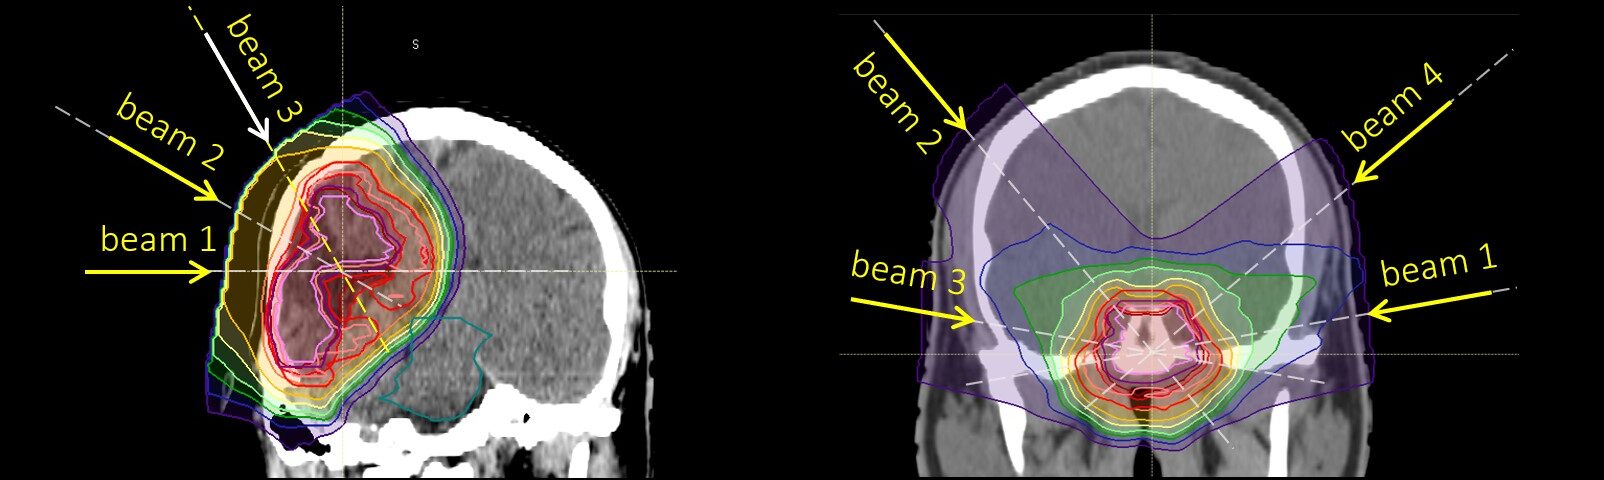

In der Krebsbehandlung ist die Partikeltherapie der neueste Stand der Technik. Dabei werden geladene Teilchen wie Protonen (oder Kohlenstoffionen) mit hoher Energie auf die Tumore gerichtet, um diese zu zerstören. Ein großer Vorteil dieser Therapieform ist, dass die Teilchenstrahlen an einer bestimmten Stelle im Gewebe gestoppt werden können, wodurch die Belastung des gesunden Gewebes verringert wird. Zu bekannten Wirkungen auf das umliegende Gewebe gehört eine als RICE (Radiation-Induced Contrast Enhancement) bezeichnete Abweichung, die in bildgebenden Verfahren einen starken Kontrast zeigt. Wie häufig, wann, mit welchem Verlauf und mit welchen Auswirkungen auf die Lebensqualität diese Veränderungen auftreten, wurde nun in einer Studie am MedAustron untersucht. Der Fokus lag dabei auf der Behandlung von Tumoren des ZNS oder in der Nähe der Schädelbasis.

„In unserer Studie untersuchten wir die Verläufe von 421 Betroffenen, die in den Jahren 2017 bis 2021 mittels Protonenstrahlen behandelt wurden“, erläutert Dr. Carola Lütgendorf-Caucig, Erstautorin der Studie und Klinische Direktorin Radioonkologie sowie Direktorin für Pädiatrische und ZNS-Partikeltherapie am MedAustron. „Zusammengefasst zeigt sich, dass die Gesamthäufigkeit von RICE mit 15 % gering und die Verläufe in den meisten Fällen symptomlos waren. Weiterführende Studien zeigten auch, dass Betroffene keine Beeinträchtigung der Lebensqualität durch RICE erfuhren.“ Ein weiteres Ergebnis der Studie war, dass der mittlere Wert (Median) von RICE-Dauer 9 Monate betrug.